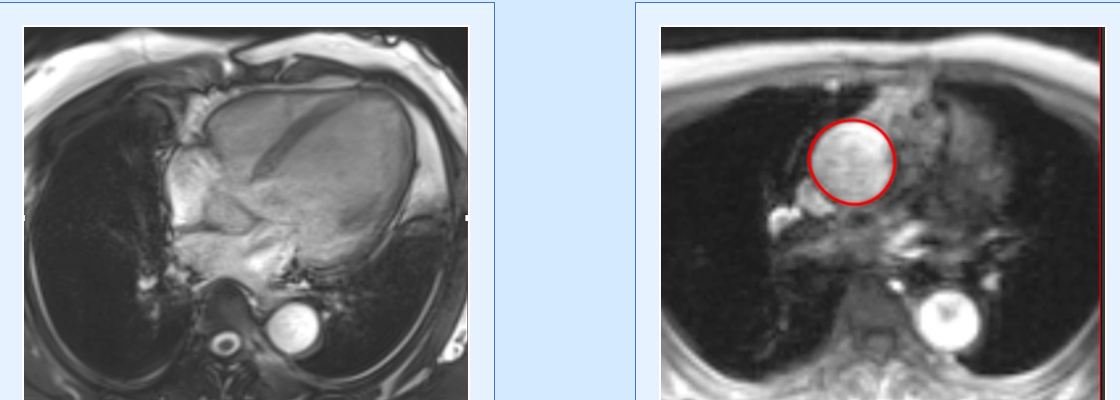

Case 229: Infective Endocarditis and Vegetations

Cardiac MRI does not show vegetations, easily especially if small. However, evaluating the transaxials through the valve may help pick up small nodules and to rule out mimics.

By Bhavin Jankharia Jan 1, 2026